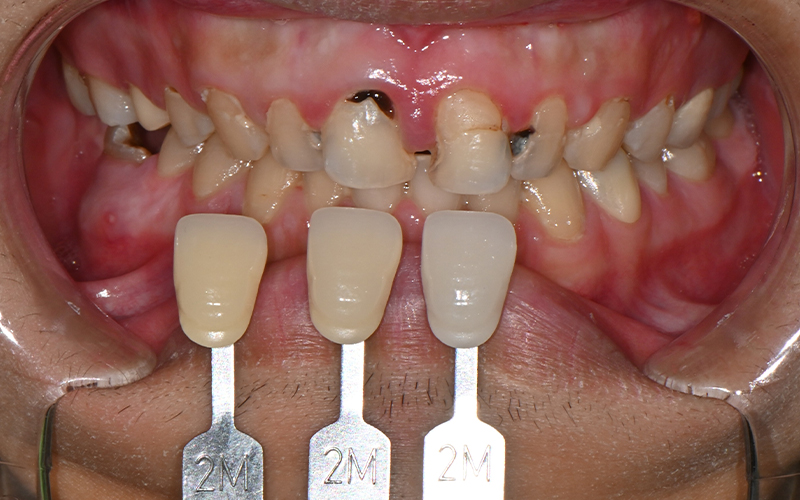

치료전 쉐이드 가이드를 통하여

치아 색상 체크도 진행해주었답니다.